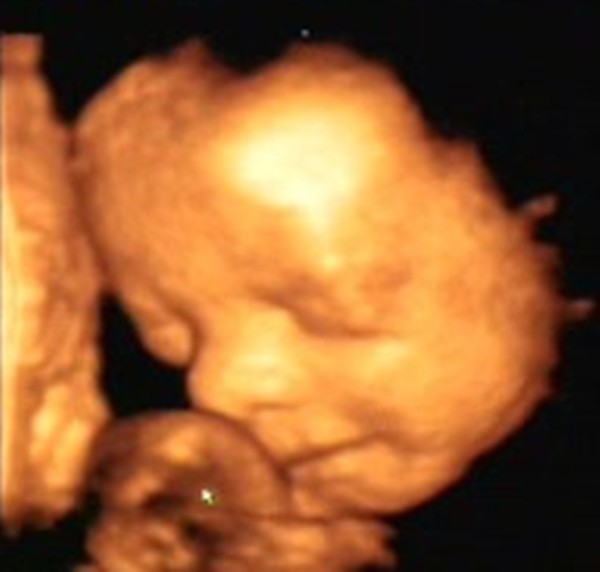

Bence 18 hetesen